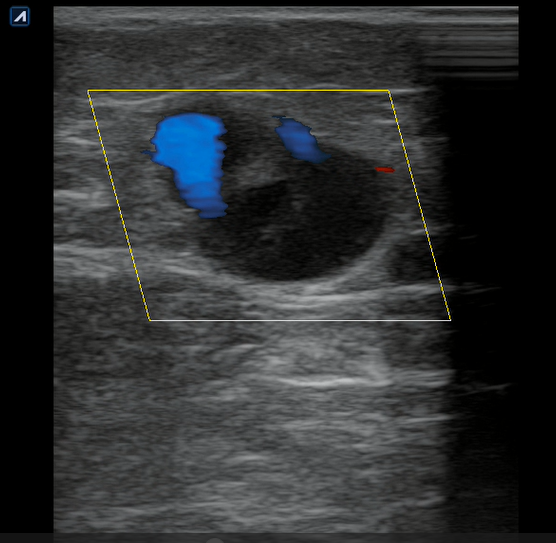

Se realiza ecografía clínica en consulta donde observamos a nivel inguinal adecuada compresibilidad de vena femoral y relleno con Doppler color. Cayado de safena libre y compresible. A 7 cm de distancia del cayado se aprecia, en territorio de safena, dilatación no compresible de la misma, contenido intraluminal ligeramente ecogénico y ausencia de Doppler color compatible con trombosis venosa superficial de 19 cm de distancia. Se estudia recorrido donde se observa en zona de dilataciones varicosas material ecogénico con ausencia de paso de Doppler alternando con zonas de paso parcial. En tercio distal de muslo comienza a desaparecer. Vena femoral profunda, poplítea y perforantes sin datos de trombosis.